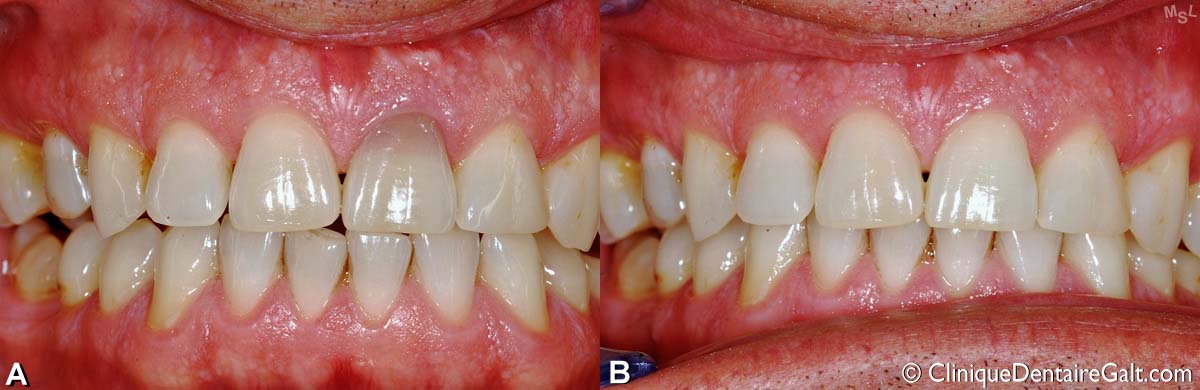

Autre exemple de blanchiment dentaire intracoronal pour une incisive supérieure décolorée. Ce traitement est fait par un dentiste généraliste. (A) Avant le traitement. (B) Après le traitement. Lorsque la dent n’est pas décolorée depuis trop longtemps, un tel traitement peut donner d’excellents résultats.

Exemple d’un blanchiment dentaire intracoronal fait par un dentiste pour une seule dent qui était décolorée. Ce genre de traitement nécessite que le dentiste “ouvre” la dent sur la face interne (linguale) et y applique des produits nettoyants. (A) Avant le traitement. (B) Après le blanchiment.